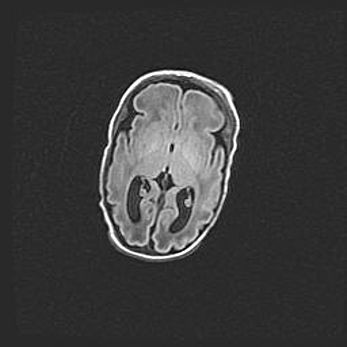

Неполная лизэнцефалия (пахигирия). Открытая гидроцефалия.

Возраст: 17 дней

Вес: 3110 г

Пол: мужской

Окружность головы: 33,5 см

Срок гестации: 35-36 недель

Лизэнцефалия—недоразвитие корковой пластинки и мозговых извилин в результате нарушения миграции нейронов коры. Поверхность мозговых полушарий гладкая. Микроскопически выявляется отсутствие нормальных слоев коры и скопление групп нейронов в подкорковом белом веществе.

Пахигирия—уменьшение числа вторичных извилин. В пораженном полушарии нервные клетки образуют толстый недифференцированный слой с неправильно расположенными нервными волокнами и группами гетеротопных клеток. Нервные клетки незрелые. Белое вещество истончено. При этом нередко аномально развит корково-спинномозговой путь.